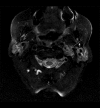

Case report: An 83-year-old woman presented with worsening episodes of dizziness of a few months duration. She also complained of tinnitus and hearing loss, more severe on the left side. Examination revealed a red bulging left-sided tympanic membrane, conductive hearing loss, and a bruit at the base of the skull. Dix-Hallpike test was negative. CT head and MRI brain revealed findings consistent with a large left-sided jugulotympanic paraganglioma, which was found to be hormonally inactive on laboratory tests. The patient underwent treatment with radiotherapy, which resulted in partial improvement of symptoms.

Conclusions: Jugulotympanic paraganglioma may manifest in the elderly with the chief complaint of intermittent vertigo, as in our case. A red bulging mass on otoscopy raises the suspicion, necessitating further investigations, including CT and MRI.